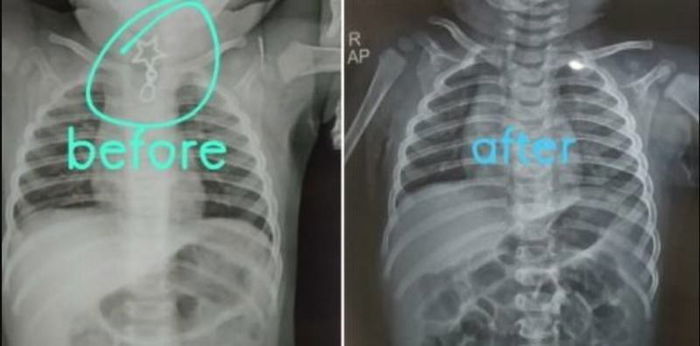

Hasil rontgen leher bayi yang menelan bandul kalung. (Linkedin/Dr Anuj Rastogi)

Tanpa pikir panjang, dokter Anuj segera melakukan rontgen dan hasilnya sungguh mencengangkan. Bandul kalung bertepian tajam itu tersangkut di area tenggorokan.